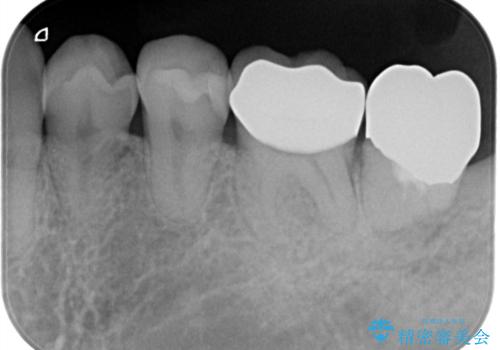

- 金属の詰め物が外れたことを主訴に来院されました。

隣の歯もむし歯を認め、セラミックインレーとセラミッククラウンにて治療を行なっております。

最後方臼歯に関しては治療介入の希望はされませんでした。